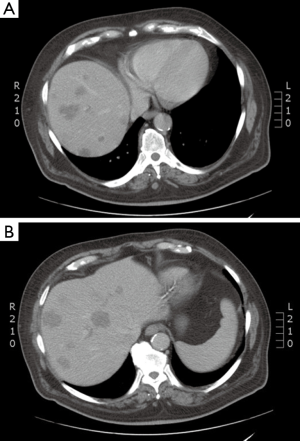

RFA, the most extensively studied ablative technique for treatment of colorectal liver metastases, is similar in intent to surgical resection. Rapidly alternating electrical current produces ionic oscillations in bipolar water molecules, which then generate frictional heat (Figure 1). An electrode probe (Figure 2) is placed within the metastatic lesion, while grounding pads are placed on the lower extremities. Energy dispersion is greatest in the vicinity of the probe generating temperatures of >100 degrees centigrade. Cell death takes place after several minutes at 50 degrees centigrade and instantaneously at temperatures of >60 degrees centigrade. Current technology can produce lethal burns of >5 cm diameter with a single probe (Figure 3). Tissue destruction is dependent on heat conduction generated from the active elements of the probe; therefore, optimal lesions are <3 cm in diameter with incomplete destruction more likely with increasing lesion size. Impediments to effective RFA include lesion location adjacent to critical structures such as bowel or central bile ducts. Flowing blood in vessels >3 mm creates a heat sink effect, drawing heat away from the treated area. Tissue charring in the vicinity of the active elements creates an insulator, which can also limit heat conduction.

Case discussion 1 (Figure 5)

A 67-year-old woman with a history of adenocarcinoma of the sigmoid colon status post sigmoidectomy presents with new onset fatigue and a rise in carcinoembryonic antigen (CEA). A CT of the chest, abdomen and pelvis, reveals new liver lesions in segments I and V, and a CT guided biopsy of the segment V reveals adenocarcinoma. As the patient had tolerated any of her chemotherapy with difficulty, medical oncology recommended liver-directed therapy. Interventional radiology reviewed her films but did not this that was an optimal situation for RFA due to possible heat sink of the central lesion and possible gastric injury for the segment V lesion. Given her low volume of disease, chemo- or radio-embolization was not warranted. Therefore, SBRT was proposed and delivered to the patient.

A 54-year-old man with a remote history of rectal cancer is found to have a new solitary liver metastasis measuring 2 cm. The patient has agreed to receive chemotherapy. RFA was recommended by the multidisciplinary liver tumor board given its long track record and good success in tumors <3 cm.